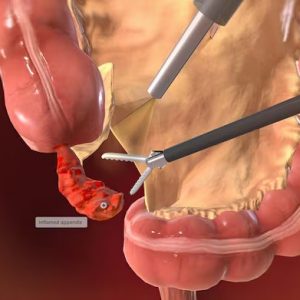

استئصال الزائدة الدودية بالمنظار

استئصال الزائدة الدودية بالمنظار هو جراحة ثقب المفتاح الآمنة والمتقدمة لإزالة الزائدة الدودية الملتهبة بأقل قدر من الانزعاج، وتعافي أسرع، وتقليل الندوب.